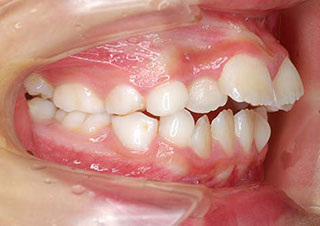

![]() |

②上顎前突(俗に言う、出っ歯):上顎前歯が下顎前歯よりも前方に離れた状態をいい、その量が 6 ~ 7mm離れていれば上顎前突の判定は「2」です。 |